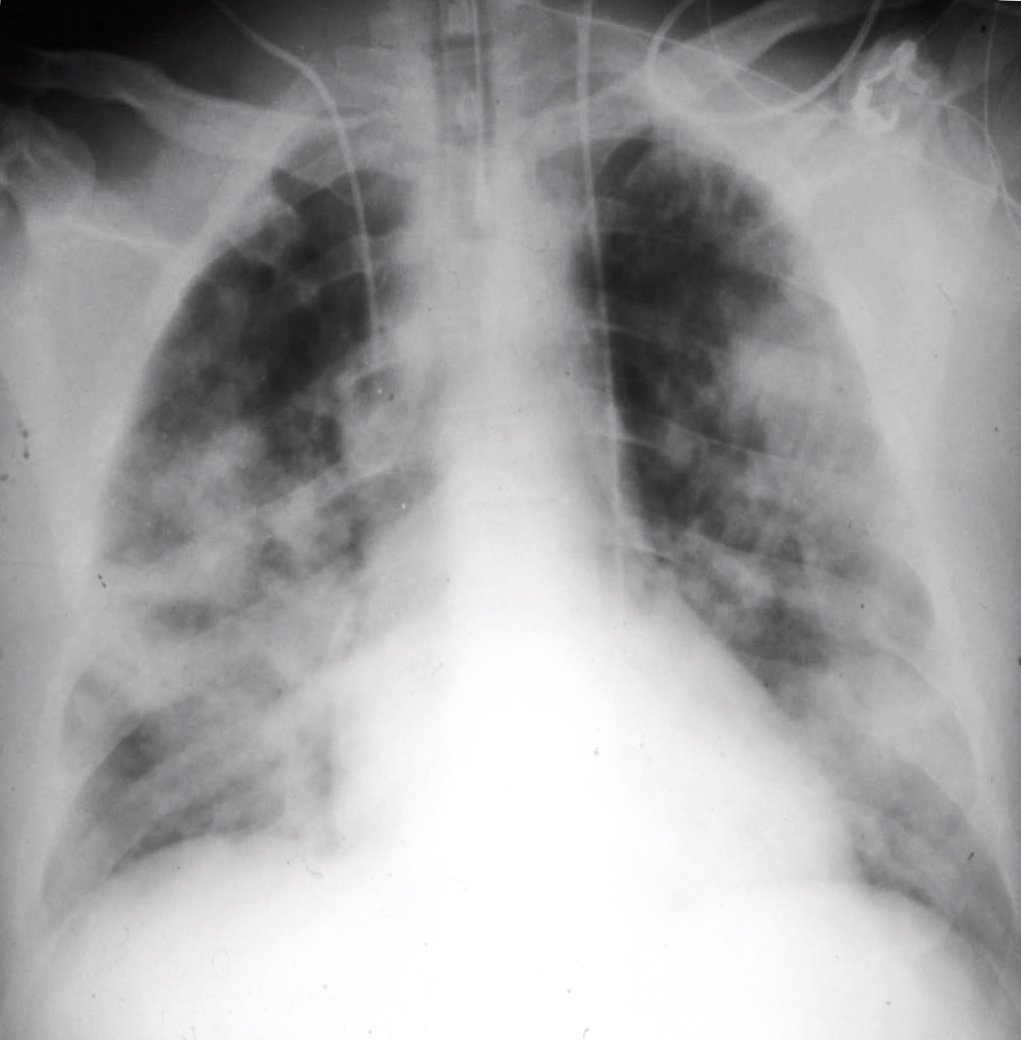

“La hiperoxemia mata y es yatrogenia pura y dura”